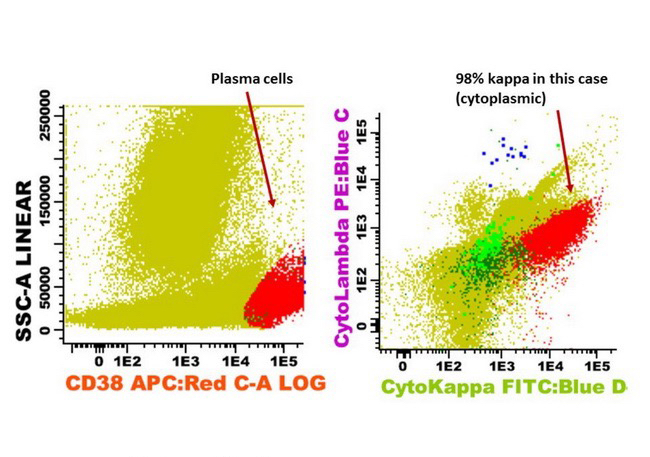

Flow cytometry description

- Monotypic cytoplasmic Ig and usually lack surface light chain

- Express CD38, CD138, often CD56+ or CD117+; may have partial CD45, usually negative for CD20, CD19 and CD10 (Cytometry B Clin Cytom 2016;90:61)

- Exception in myeloma with t(11:14) where plasma cells more often express B cell markers including CD19 and CD20